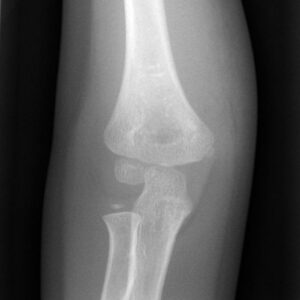

[toggle title=”Radiokapitellar Hat” state=”close”]

AP, Lateral ve Oblik grafilerde radius başının ortasından geçecek şekilde çekilen çizgi kapitulumun ortasından geçmelidir.

Bu hat üzerinde herhangi bir sapma radius başı çıkığını düşündürür. Bunun dışında lateral kondil kırıklarında da bu hat üzerinde bozulma görülebilir.

Radiokapitellar Hat Kapitulumun medialinde kalmış